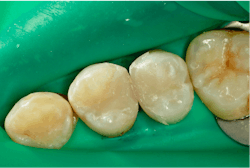

Once the restoration is finished, the rubber dam is removed and the occlusion is checked. Finally, a quick polish is done with a single-step polishing system, the Optragloss. At this point, we have created a great interproximal contact for Lee and restorations that should last very well while we continue to restore his other carious lesions (figure 13).

A post-op bitewing radiograph shows successful restorations for Lee (figure 14).